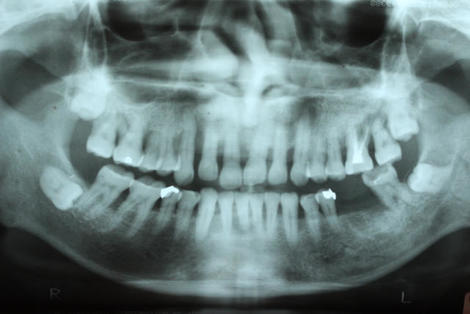

平成12年に初診で来院、レントゲン写真を見ていただくと、特に上顎ですが、全体的に歯周病が進んでいて動揺もありました。

残念ながら、右上1番、左側の7.8番はどうしても保存ができなかったため抜歯。

リーゲルテレスコープで内冠を連結し、外冠を製作して完成させました。

右上の2番を孤立させているのは、動揺があり、近い将来保存が難しいだろうと予測して離しておきました。